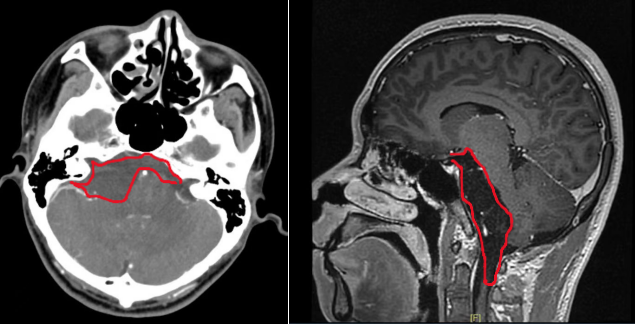

患者李先生(化名),二十多岁,因头晕、听力下降、走路不稳三个月,来到我院神经外科门诊找到郝少才主任就诊。颅脑核磁共振检查结果提示:桥小脑角区竟潜伏着一颗大小超6厘米的巨大肿瘤!这颗肿瘤范围上至鞍上压迫视神经,下至枕骨大孔区,脑干压迫明显且腹侧也有肿瘤生长。肿瘤包绕动眼神经、外展神经、三叉神经、面听神经以及后组多根颅神经,此外也包绕椎基底动脉及其主要分支。

▲术前影像学检查(CT、MRI)